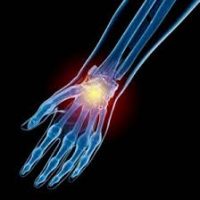

Прилагайки една от най-ефективните терапии за лечение на сухожилия и лигаменти, благодарение на огромния опит и екпертиза на доктор Кавалино ние сме способни да помагаме на хора из цяла България да спрат да чувстват болка.